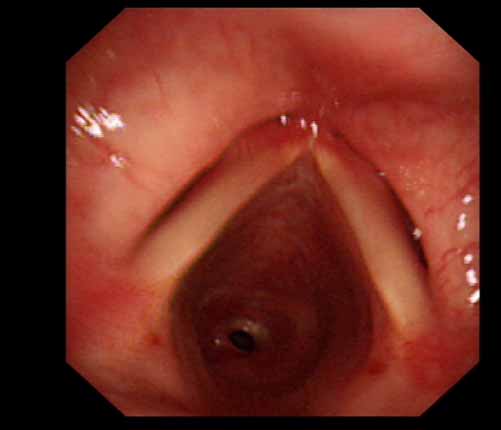

患者李某某,女,45歲,因氣管插管咳嗽、喘憋10天入院。頸部CT檢查示聲門下約20mm處氣管明顯狹窄,狹窄段長約26mm,最窄處直徑約4.4mm。支氣管鏡檢查見聲門下約2cm氣管呈漏斗狀縮窄,直徑約4-5mm,支氣管鏡無法通過。經(jīng)科室討論,決定行電子支氣管鏡下氣管球囊擴(kuò)張治療。與患者及家屬充分溝通并經(jīng)三方見證談話簽署知情同意書后,在患者持續(xù)吸氧、局麻下,科主任于世倫主任醫(yī)師帶領(lǐng)治療小組為患者實(shí)行電子支氣管鏡下氣管球囊擴(kuò)張術(shù)。手術(shù)過程順利,出血量很少,術(shù)后患者呼吸困難癥狀即可明顯緩解。10天后行二次擴(kuò)張,患者日?;顒訜o明顯喘憋,二次術(shù)后5天出院。

術(shù)前聲門下的漏斗樣狹窄口 術(shù)中球囊擴(kuò)張 術(shù)后擴(kuò)張開的氣管管腔